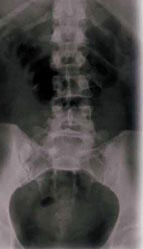

Les résultats ont montré qu'à la fin de l'étude, les femmes prenant la dose d'isoflavones la plus élevée avaient des effets significativement bénéfiques sur leur perte osseuse, particulièrement sur la colonne vertébrale et le col du fémur.

La supplémentation avec 126 mg d'isoflavones a augmenté la densité minérale osseuse de 0,36 % dans la colonne vertébrale, contre une perte de 1,42 dans le groupe placebo.

Les niveaux urinaires de Dpd ont augmenté de 30 % dans le groupe placebo, indiquant un amincissement de l'os, alors qu'une diminution de 3,8 % était observée dans le groupe prenant la plus forte dose d'isoflavones. Les chercheurs en ont conclu que les isoflavones de soja avaient un effet positif dose dépendant sur l'atténuation de la perte osseuse sur la colonne vertébrale et le col du fémur.